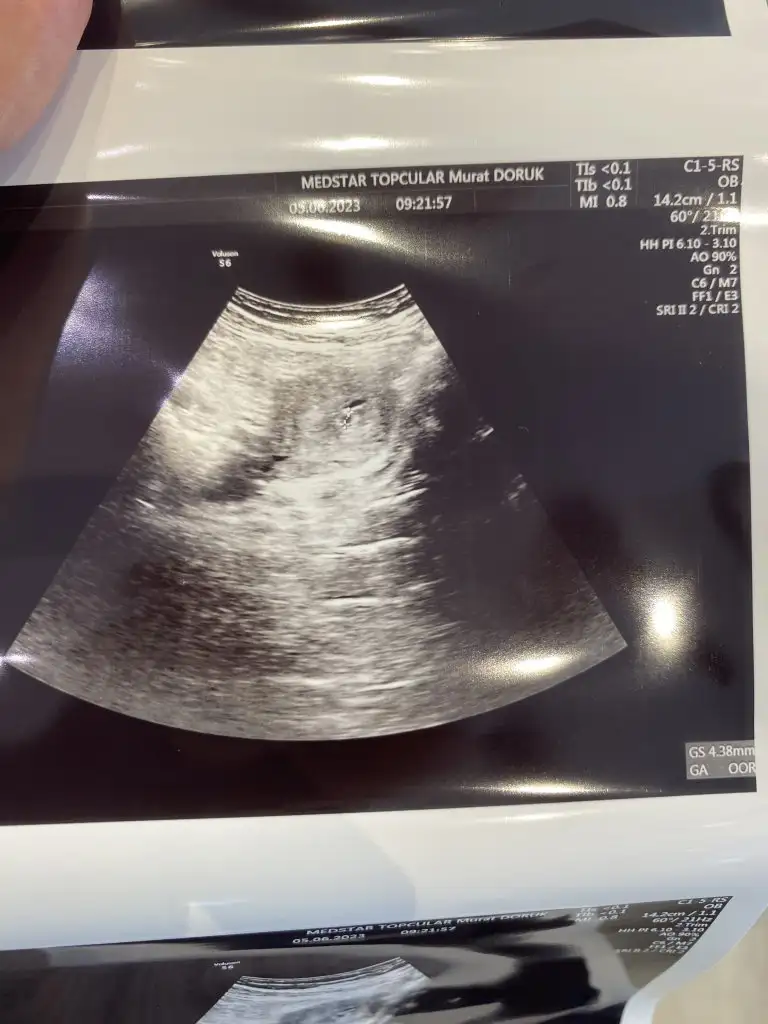

Evet canım bayagı minikt doktorumu tanımasam bu doktor bişi bilmiyor bu kese demezdim.bak orda doktor işaretlemiş görüyormusun minicik var yok arası

Ay aynı aynı benimde böyle aynısı hatta bit kadar bir nokta çıktı o da böyle ölçtü ama çok küçük emin olamıyorum dedi 🙏🏻 çok içim rahatladı demek o gördüğümüz keseymiş